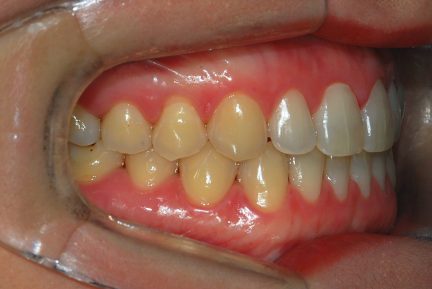

État final

Résultats obtenus

- Relation de classe I obtenue

- Guidage fonctionnel des canines des deux côtés

- Articulé antérieur corrigé

- Articulé postérieur corrigé

- Surplomb et recouvrement normaux obtenus

- Lignes médianes coïncidentes

- Alignement des deux arcades par dérotation

- Forme de l'arcade améliorée

- Cas où tous les objectifs du traitement ont été atteints